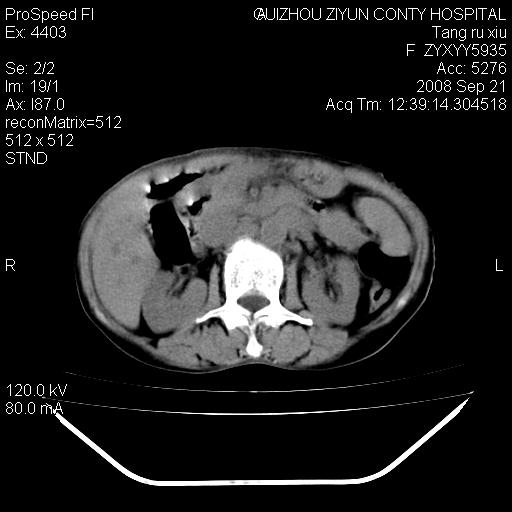

f、57岁,上腹痛.2月,近来胸闷。2月前在外院摄胸片示左侧胸腔少量积液。

(患者腹痛入院,欲吐,临床医生说禁饮,所以没有口服对比剂)

肝脏大小形态尚可,其实质内可见多发大小不等的低密度影,边缘模糊。肝门区结构紊乱,腔静脉腹主动脉旁可见多发软组织密度影,部分融合成团块状,并向下延伸。胰腺及十二指肠结构显示不清。腹腔内脐后肠管走形僵硬,管壁可见增厚。盆腔内可见多个淋巴结影。所扫层面左侧胸腔可见大量弧形水样密度影,其内侧可见被压缩的肺组织影。左侧胸壁可见一小结节样软组织密度影,边缘模糊。心脏纵隔向右侧移位。心脏包膜内可见囊样低密度影,其内侧心房室周围可见一圈气体样密度影。纵隔内大血管旁可见多发软组织团块影,部分融合。

1.腹膜后淋巴瘤侵及肝脏,肺内及纵隔内多发转移。2.左侧大量胸腔积液并压缩性肺不张。3.心包脓肿可能,转移不除外。4.脐后局部肠管管壁增厚,考虑炎症可能,肿瘤不除外。